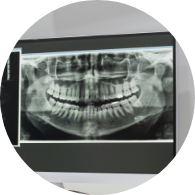

자료채득

X-ray, 구강 내ㆍ외 카메라 사진, 치아 모형, 턱관절 및 치주 상태, 전신 질환 유무, 가족력 검사 등을 ​​​​​​​통해 진단 자료 수집